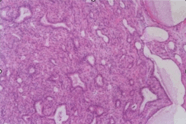

图片显示的是乳腺病变

该乳腺病变的组织学特点是

• A.一般不形成小叶结构,腺体衬覆单层立方上皮,没有肌上皮

• B.小叶扩大,腺泡导管化

• C.小叶结构尚存,增生的腺管受挤压明显,呈长圆形,外围肌上皮

• D.只有导管形成,一般不形成小叶

• E.形成小叶结构,增生的腺管受挤压明显,呈长圆形,外无肌上皮

该乳腺病变最可能的病理诊断是

• A.小叶增生

• B.硬化性腺病

• C.盲管腺病

• D.微小腺体腺病